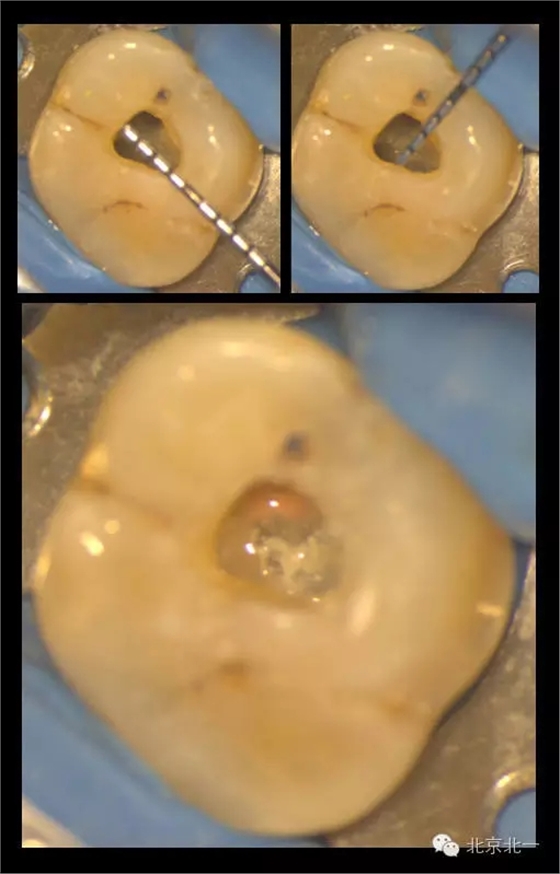

再看我們的現(xiàn)實,在我們的日常工作中,也一直期望能對微創(chuàng)開髓多有嘗試,可惜的是由于我國患者的口腔保健意識還有待提高,很多來牙髓病專科就診的患者牙體本身由于病變已沒有微創(chuàng)的可能。前段時間終于等到了這么一例牙周牙髓聯(lián)合病變,患者有著強烈的保留牙齒的愿望,但在牙周治療中并發(fā)了牙髓炎的癥狀,因此轉診至牙體牙髓??菩枰M行根管治療。

對于這個冠部牙體組織完好的病例,我們也確實想給她盡量保留健康組織,于是就開始了對這個病例的微創(chuàng)治療。

根充完成后,用樹脂對牙齒進行了充填(由于是急診患者,很遺憾忘了拍攝術前照)。